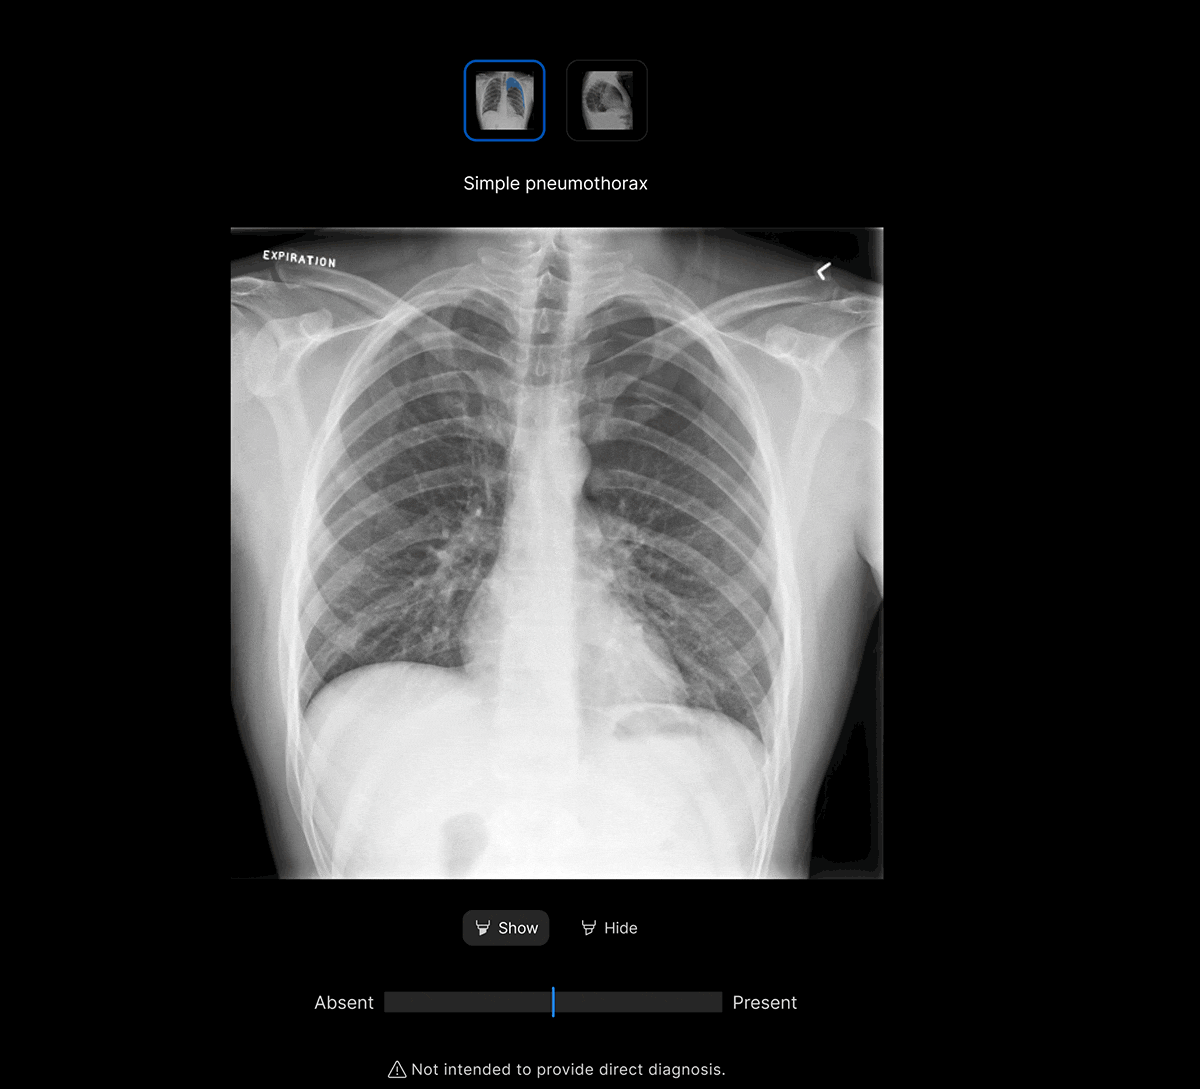

Customisable features.

Customisable thresholds for individual findings (to optimise for sensitivity / specificity), to tailor the workflow to your clinical setting or population.

Intuitive UI. Powerful AI.

Designed by radiologists.

Designed to reduce cognitive load.